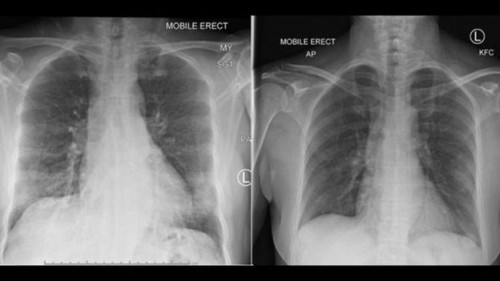

Η μελέτη έγινε σε ασθενή με ήπια συμπτωματολογία, χωρίς βεβαρημένο ιστορικό υγείας. Πρόκειται για μια 47χρονη γυναίκα από τη Γουχάν της Κίνας που νοσηλεύθηκε σε νοσοκομείο της Αυστραλίας και ανάρρωσε μέσα σε 14 ημέρες.

Η Δρ. Kedzierska δήλωσε στο BBC ότι η ομάδα της εξέτασε «όλο το εύρος της ανοσολογικής απόκρισης» στην ασθενή. Τρεις μέρες πριν η κατάσταση της υγείας της να αρχίσει να βελτιώνεται, συγκεκριμένα κύτταρα παρατηρήθηκαν στο κυκλοφορικό της. Σύμφωνα με τη Δρ. Kedzierska, τα ίδια κύτταρα ενεργοποιούνται, σε αντίστοιχο χρονικό διάστημα πριν από την ανάρρωση, στην περίπτωση της κοινής γρίπης.